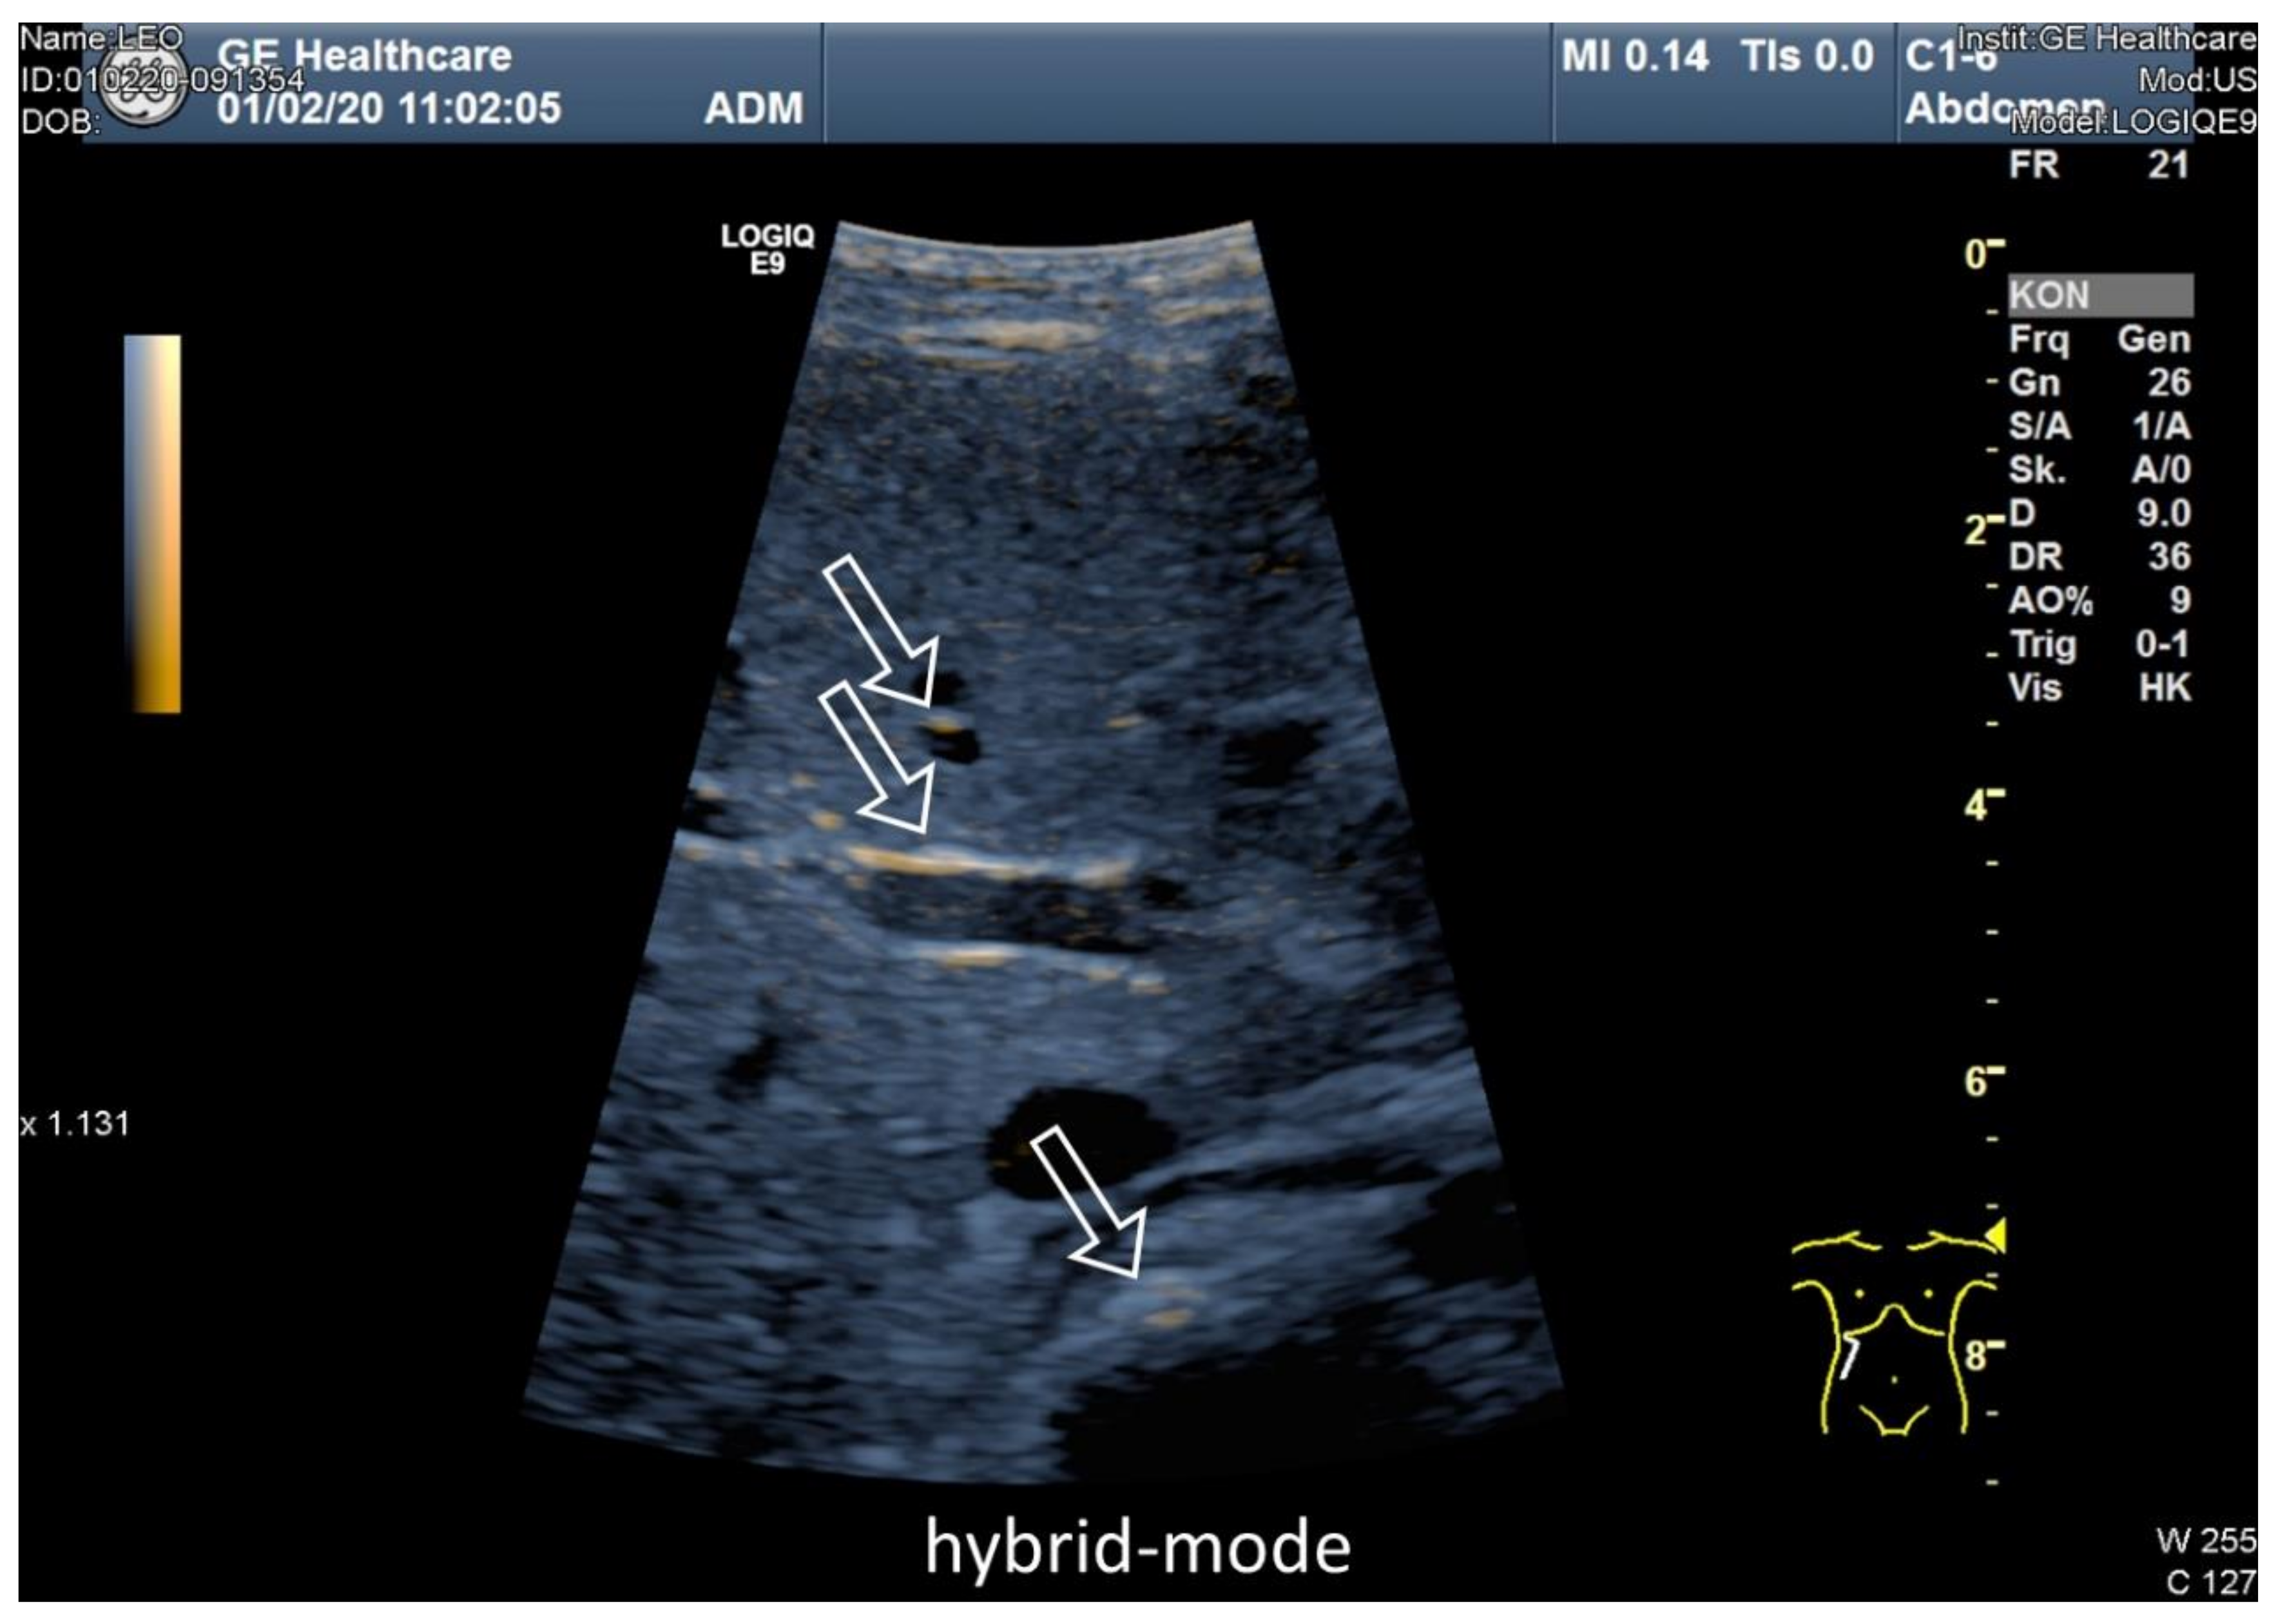

3.3. Ultrasound Examination of Intestinal Absorption